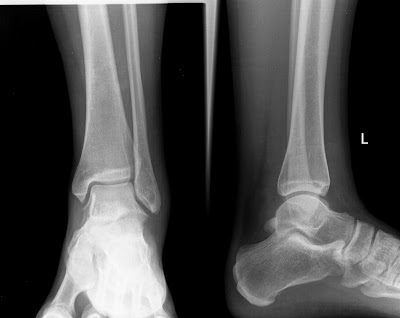

| LTFA: ant. talofibular lig., FL: fluid, AV: avulsion |

- Ligamentous injury